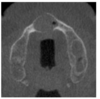

mental foramen